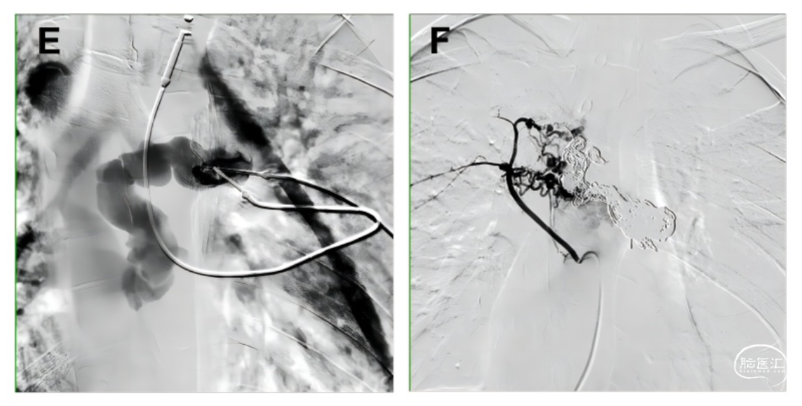

上海九院介入科随即为该患者实施了局部直接穿刺下的弹簧圈联合无水乙醇栓塞治疗(图E),术后六个月复查,该患者的神经症状得到了明显改善,复查造影结果显示畸形血管团完全闭塞,无血管再通(图F)。